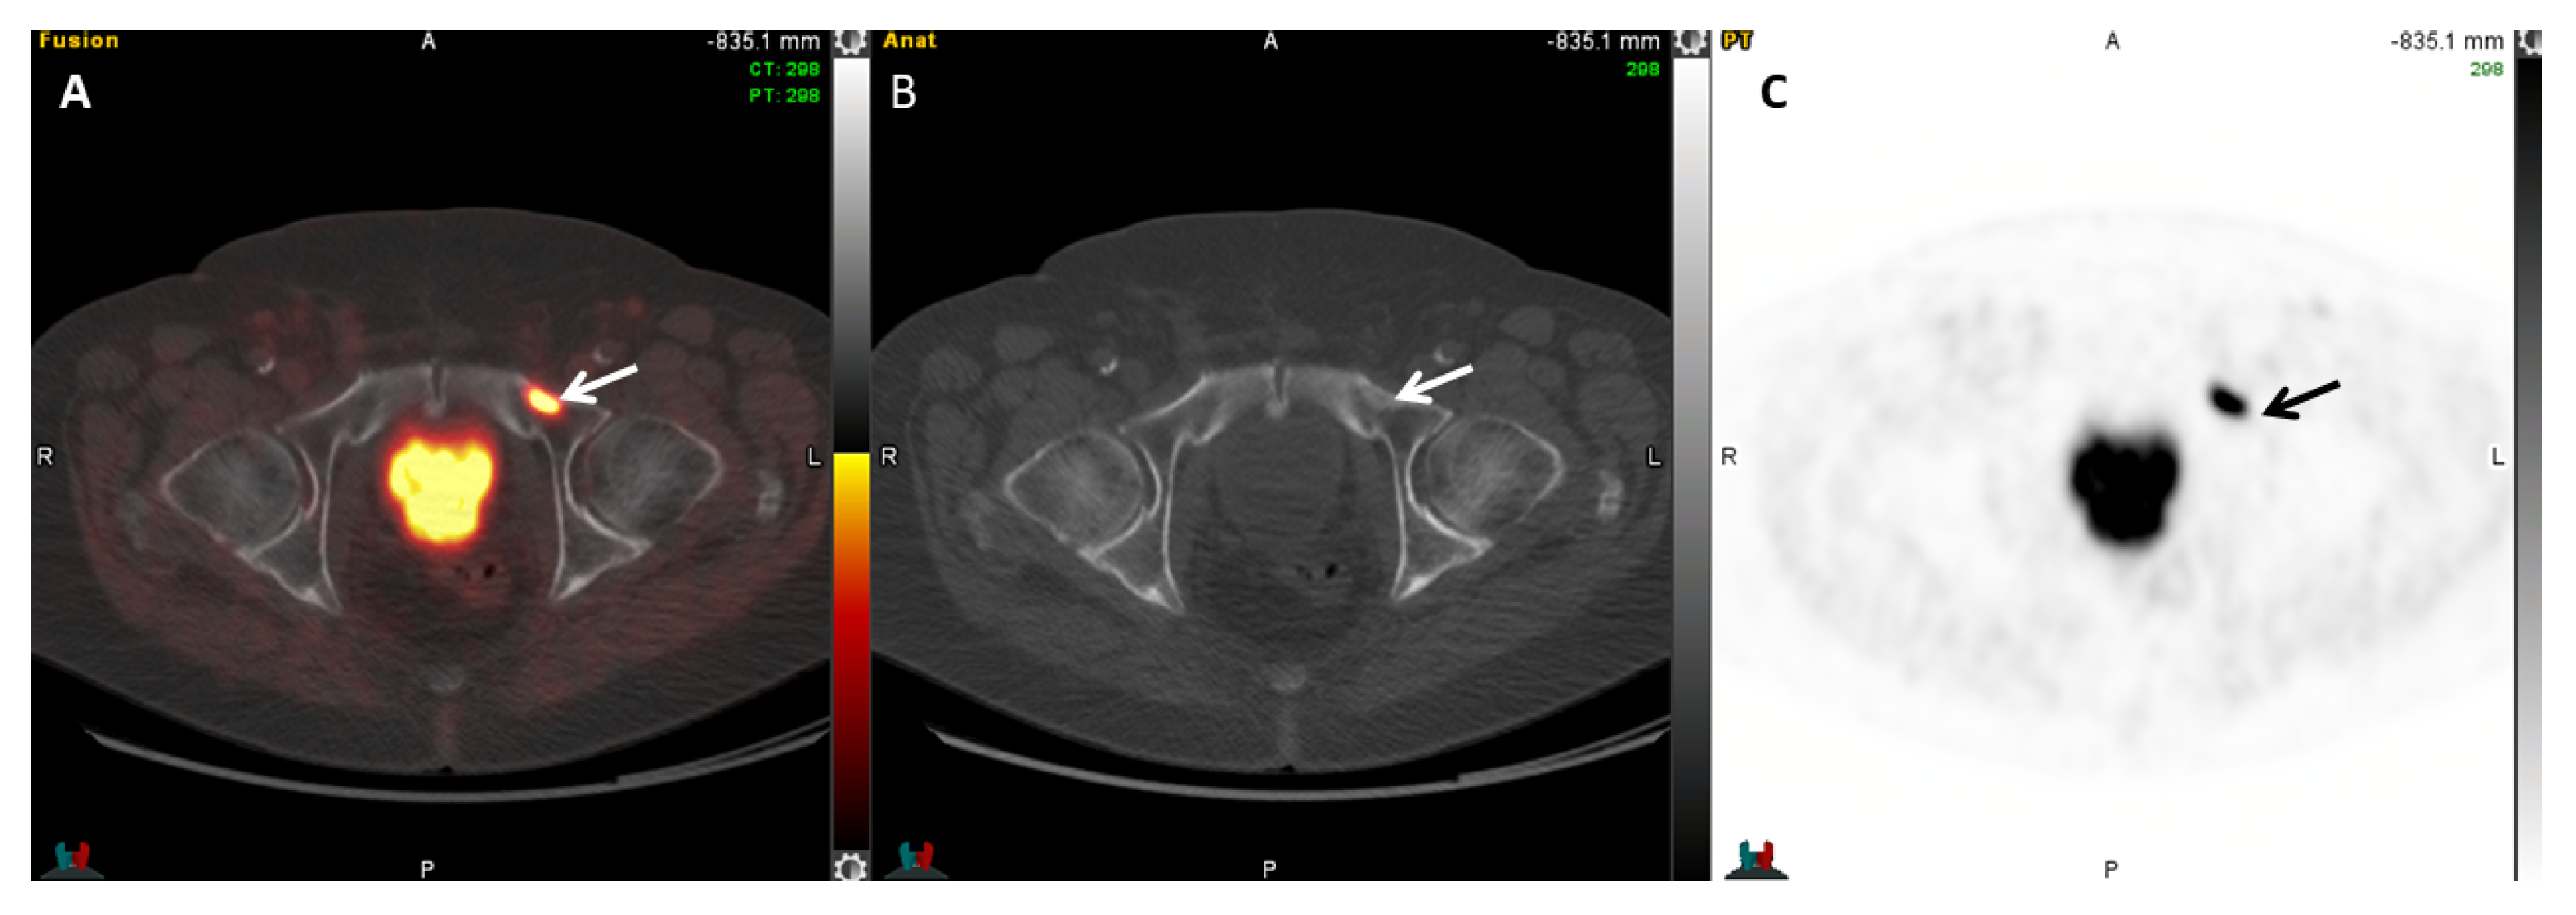

2.5.5. 18F-PSMA-1007